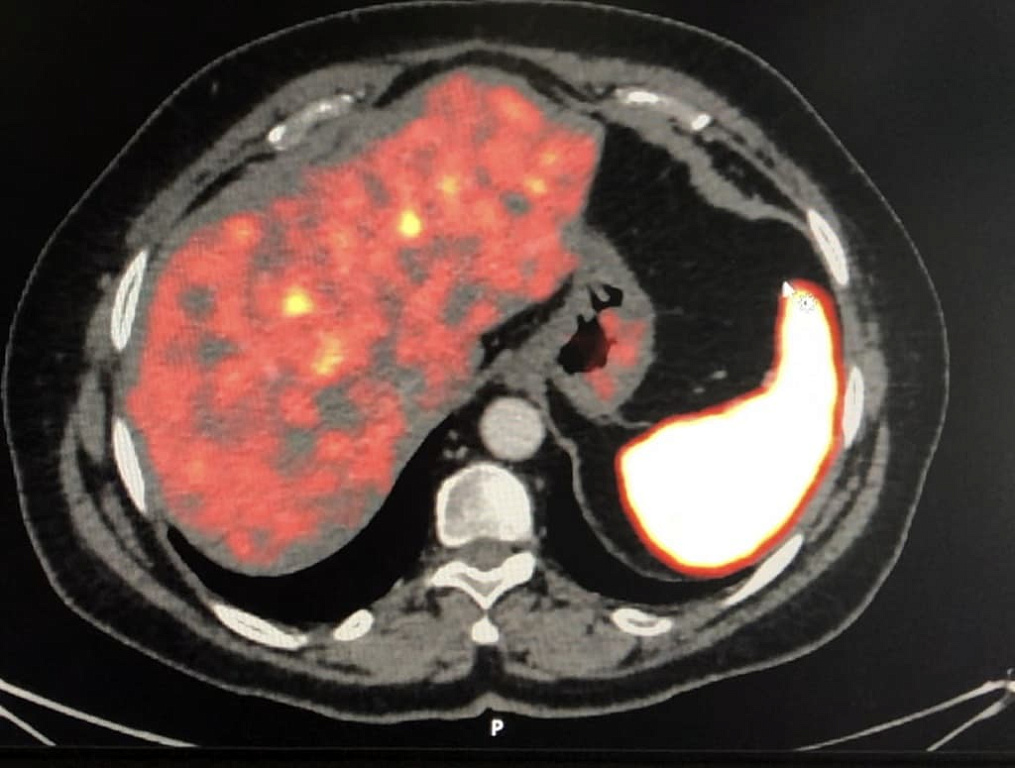

• ПЭТ-КТ с галием (68Ga-DOTATATE и 68Ga-DOTANOC),

• ПЭТ-КТ с глюкозой (ФДГ)